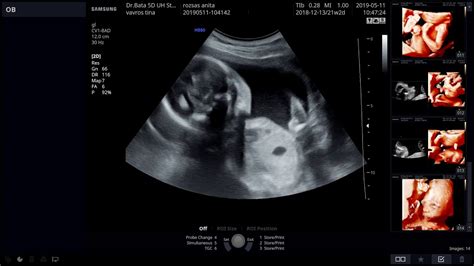

II. trimeszteri (18-22 hetes) ultrahang szűrővizsgálat

A terhesgondozás kötelező része a 18-22. hét között elvégzett szülészeti-genetikai ultrahang. A szűrővizsgálat célja a magzat, magzatok szívműködésének a kimutatása, a terhességi kor pontosítása, a magzat méretének, növekedésének ellenőrzése, az alapvető magzati anatómia ábrázolása, egyes magzati fejlődési rendellenességek felismerése, a magzatvíz mennyiségének, a lepény szerkezetének, elhelyezkedésének a megítélése. Ebben a terhességi korban történik a legtöbb, ultrahanggal észlelhető fejlődési rendellenesség szűrése. Ez a szűrőteszt tulajdonképpen az anatómiai szűrővizsgálat, mivel a magzat mérete már nagyobb, így a belső szervei is megfelelően vizsgálhatók. A vizsgálat elsődleges célja az ajak és a szájpad hasadék, a nyitott gerinc és a dongaláb szűrése. A szívhibák felismerésében is fontos szerepet játszik. Ekkor már biztosan megállapítható a magzat neme is, de fontos tudni, hogy az orvosok igyekeznek alkalmazkodni a család preferenciájához, ha meglepetésnek szánták a leendő gyermekük nemét.